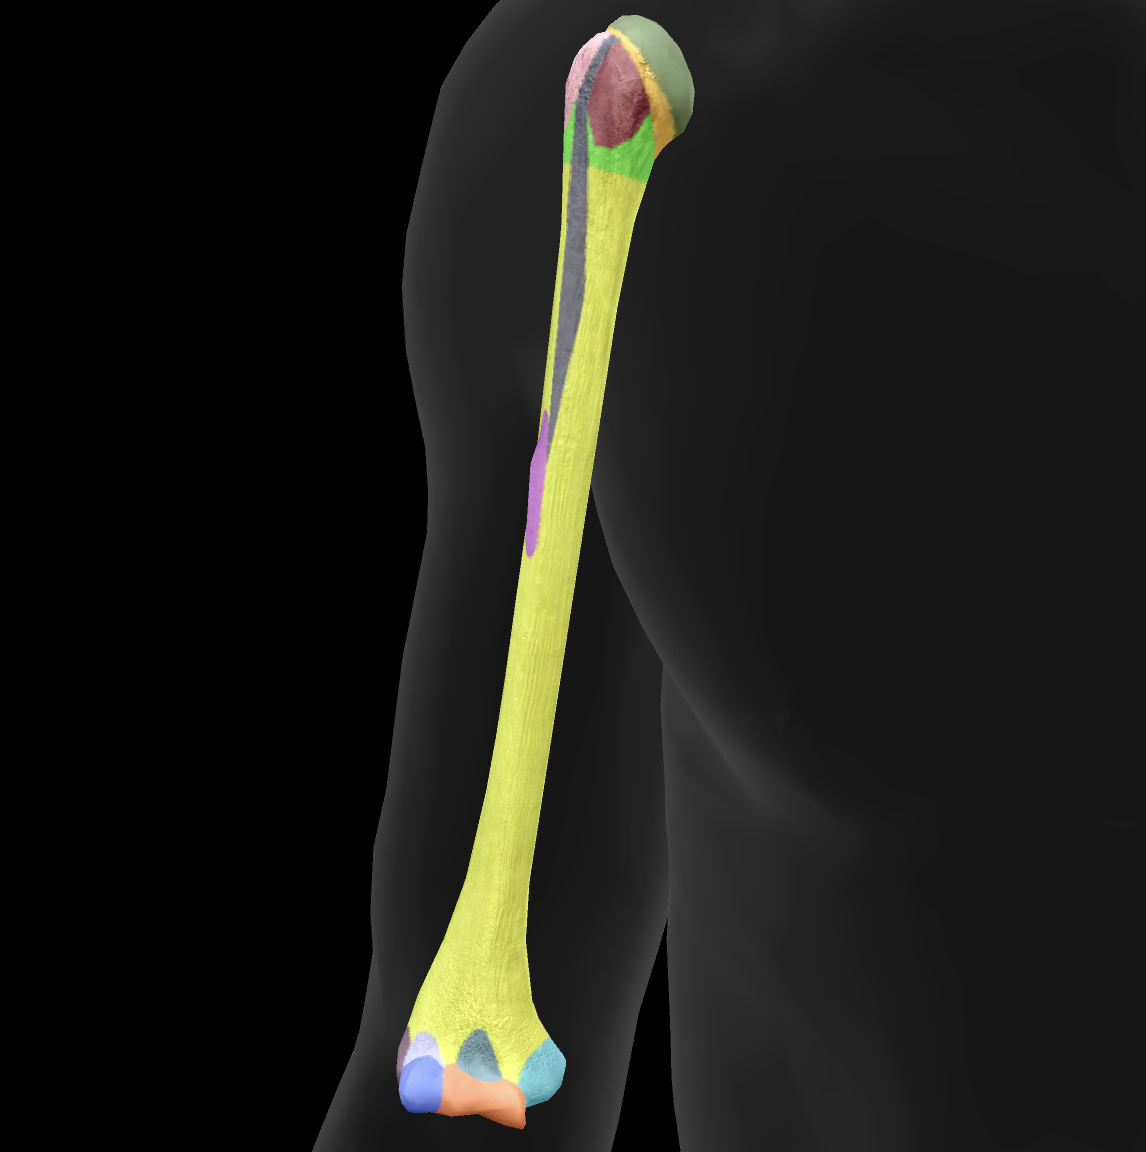

What bone is this?

humerus

What is this boney landmark?

head

What is this boney landmark?

anatomical neck

What is this boney landmark?

surgical neck

What is this boney landmark?

lesser tubercle

What is this boney landmark?

bicipital grove

What is this boney landmark?

deltoid tuberosity

What is this boney landmark?

shaft

What is this boney landmark?

capitulum

What is this boney landmark?

trochlea

What is this boney landmark?

radial fossa

What is this boney landmark?

coronoid fossa

What is this boney landmark?

medial epicondyle

What is this boney landmark?

lateral epicondyle

What is this boney landmark?

greater tubercle

What is this boney landmark?

radial grove

What is this boney landmark?

olecranon fossa

What is this boney landmark?

lateral supracondylar ridge

What is this boney landmark?

medial supracondylar ridge